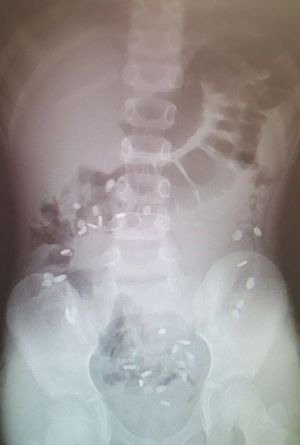

A 2 yr old child was brought to ER for abdominal pain.👆

Dx? ?

Lots of foreign bodys

But what are the foreign bodies?

Ingestion of foreign bodies